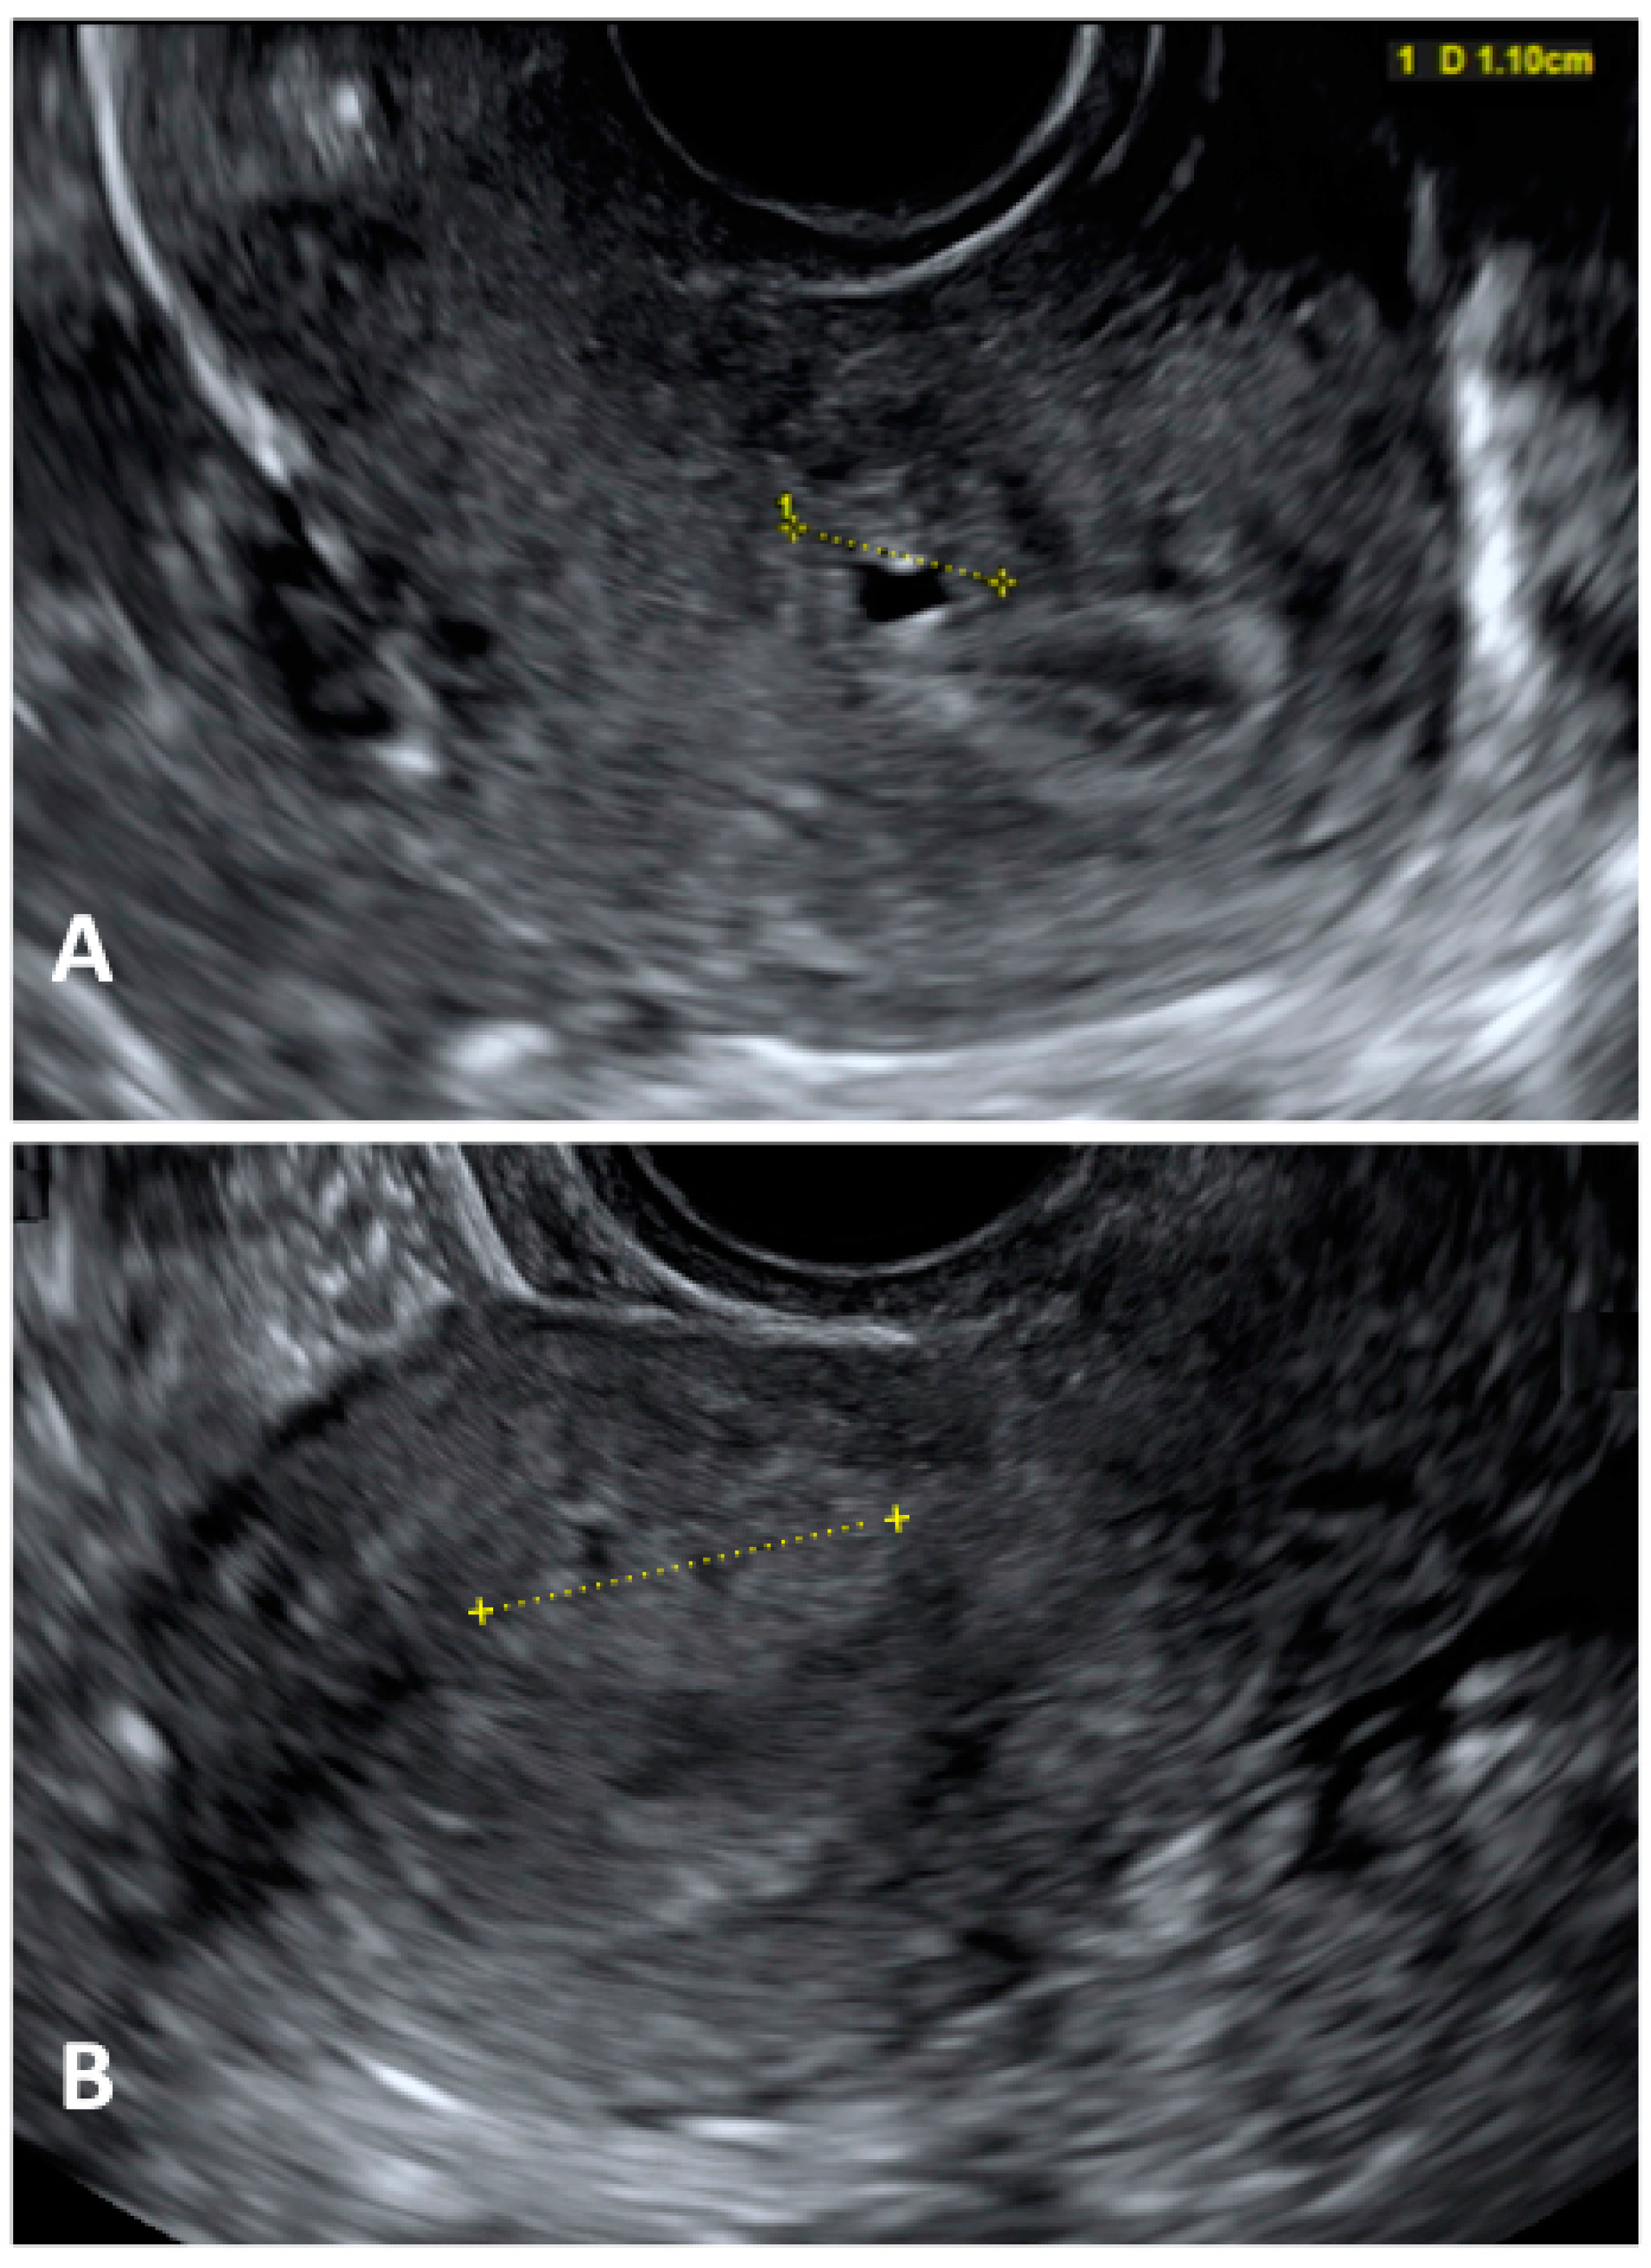

- Martire, F.G.; Lazzeri, L.; Conway, F.; Siciliano, T.; Pietropolli, A.; Piccione, E.; Solima, E.; Centini, G.; Zupi, E.; Exacoustos, C. Adolescence and endometriosis: Symptoms, ultrasound signs and early diagnosis. Fertil. Steril. 2020, 114, 1049–1057. [Google Scholar] [CrossRef]

- Martire, F.G.; Russo, C.; Selntigia, A.; Nocita, E.; Soreca, G.; Lazzeri, L.; Zupi, E.; Exacoustos, C. Early noninvasive diagnosis of endometriosis: Dysmenorrhea and specific ultrasound findings are important indicators in young women. Fertil. Steril. 2023, 119, 455–464. [Google Scholar] [CrossRef]

- Exacoustos, C.; Lazzeri, L.; Martire, F.G.; Russo, C.; Martone, S.; Centini, G.; Piccione, E.; Zupi, E. Ultrasound Findings of Adenomyosis in Adolescents: Type and Grade of the Disease. J. Minim. Invasive Gynecol. 2022, 29, 291–299.e1. [Google Scholar] [CrossRef]